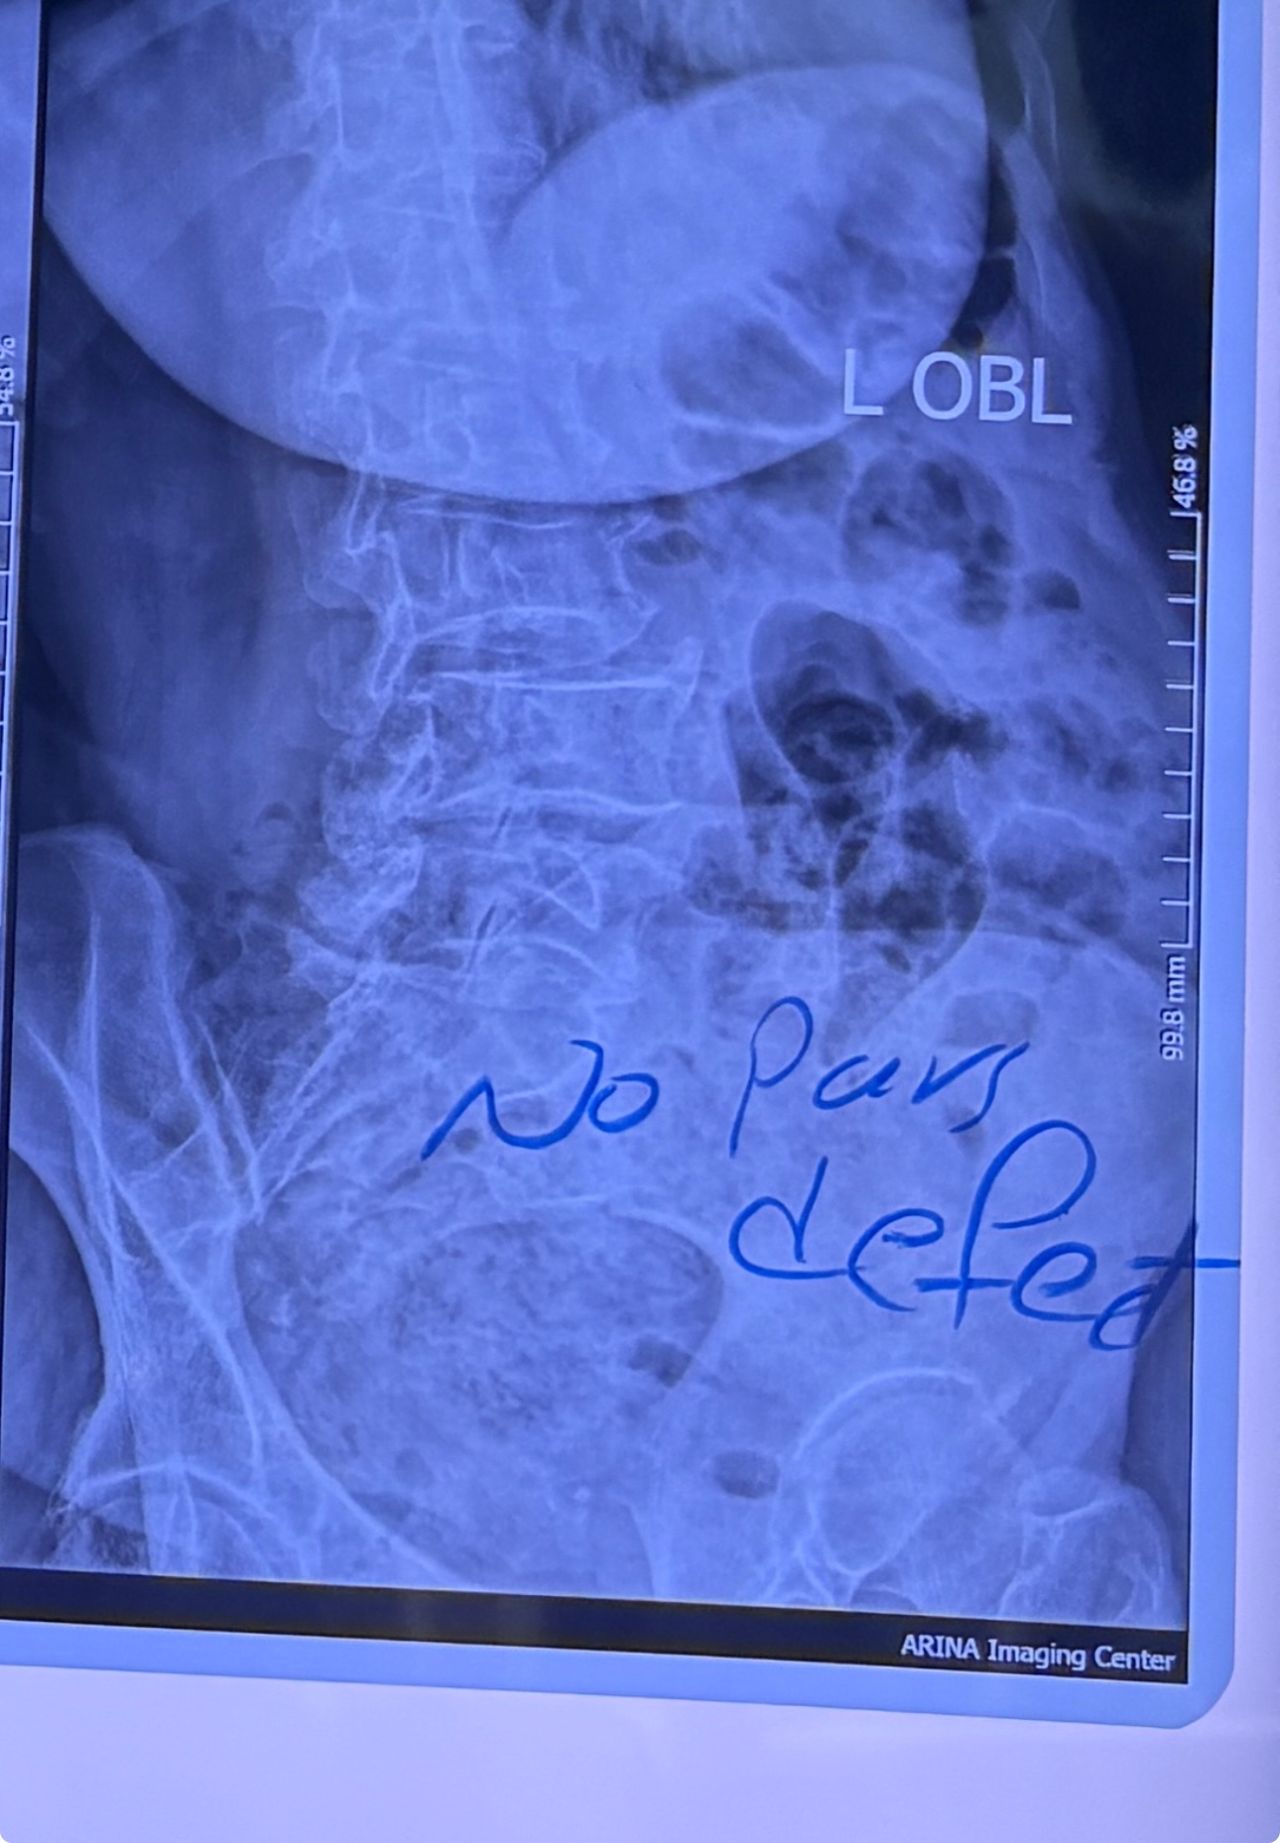

L4-L5 level:

sever L4-5 canal stenosis mainly due to FL hypertrophy?

CSF block. Mild L3 retrolisthesis, facets hypertrophy bilateraly causing L and R IVF stenosis, disc hyperbule

Since I’ve noticed instability in some segments I asked for dynamic L/S x ray:we see mild L4 ant listens due to DjD/DDD. There is not any pars defect.

I will give her treatment via Cox chiropractic flex dis and axial decompression. I would use DTS decompression

Since there is a few mild to moderate DjDs/ DDs in her lower back I won’t use lumbar adjustment on her